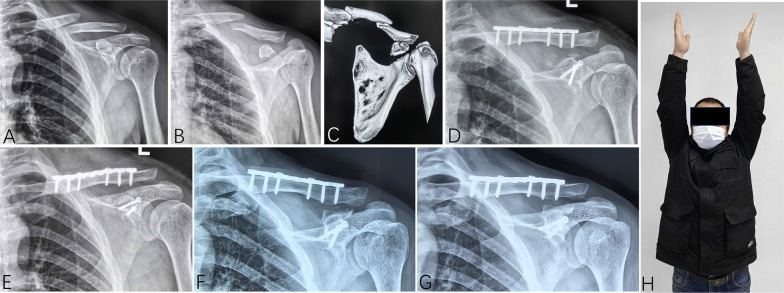

Results: From October 2012 to February 2023, 40 patients were diagnosed with ipsilateral fractures of the clavicle and coracoid process of the scapula, accounting for 1.4% (40/2877) of all clavicle fractures and 5.2% (40/786) of all scapular fractures. This study included 27 patients with follow-up exceeding 12 months: 6 had medial-third clavicle fractures, 12 had middle-third fractures, and 9 had distal-third fractures. According to Eyres' classification, the coracoid fractures included two type I, five type II, eight type III, seven type IV, and five type V fractures. Twenty-two patients received operative treatment, with clavicle fractures fixed with internal plating and 11 coracoid fractures with internal fixation. Bone union was achieved in all patients. The mean Constant-Murley score was 91.2 ± 9.4 and the mean DASH score was 6.4 ± 7.6. Five patients reported mild shoulder pain and five patients developed complications.

Conclusions: Ipsilateral concomitant fractures of the clavicle and coracoid process can occur at various clavicle locations, with shaft and medial fractures more common than previously thought. Displaced fractures can be effectively managed with operative treatment, and coracoid process fixation may not be necessary if satisfactory indirect reduction is achieved after clavicle fixation.